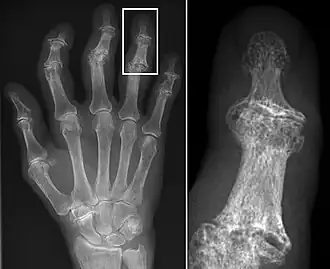

Erosive lesions and marginal lipping associated with hand OA.

Osteoarthritis (OA) is a degenerative joint disease that affects the junctions of articulating elements, or synovial joints (e.g. knee, shoulder) and is characterized by the damage of cartilage. OA is the most commonly documented pathology found in archaeological human remains and has been used extensively as an activity marker that reflects stress-related activity patterns or occupation.[11] Factors such as age, sex, body size and others also affect its expression.[12]